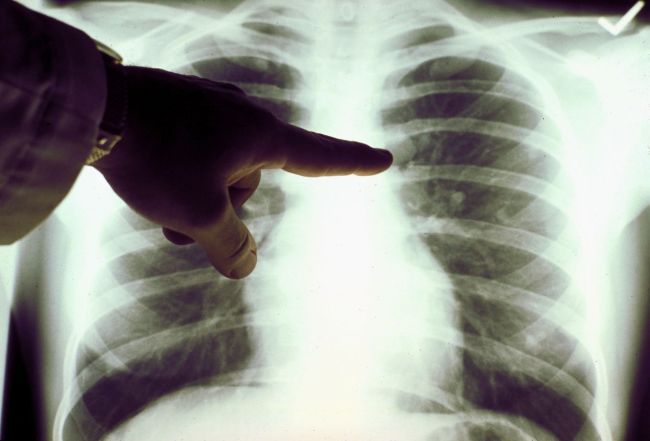

Ο καρκίνος του πνεύμονα (ΚτΠ), μεταξύ των καρκίνων, παραμένει με διαφορά ο πρώτος σε θνητότητα και τούτο διότι συνήθως διαγνώσκεται σε προχωρημένο στάδιο λόγω απουσίας συμπτωμάτων στα αρχικά στάδια της νόσου,με αποτέλεσμα χαμηλή 5ετή επιβίωση. Η εκστρατεία ενημέρωσης για την επικινδυνότητα αυτή και την αξία του προσυμπτωματκού ελέγχου ιδίως σε ομάδες υψηλού κινδύνου, όπως οι χρόνιοι καπνιστές, είναι ζωτικής σημασίας, καθ ́ όσον σώζει στη κυριολεξία ανθρώπινες ζωές.

Το Ελληνικό Διαδημοτικό Δίκτυο Υγιών Πόλεων του Π.Ο.Υ, μέλος του οποίου είναι ο Δήμος Αγρινίου, σε συνεργασία με την Εταιρεία Νοσημάτων Θώρακος Ελλάδας – ΕΝΘΕ, ξεκίνησε στους Δήμους – μέλη του Δικτύου, πανελλήνιο Πρόγραμμα ενημέρωσης και ευαισθητοποίησης του πολίτη για την αξία της πρώιμης διάγνωσης του ΚτΠ με τον διακριτικό τίτλο «ΜΕΛΙΤΗ».

Σκοπός του προγράμματος είναι η ενημέρωση των πολιτών για τη σημασία του προσυμπτωματικού ελέγχου του ΚτΠ με ετήσια χαμηλής δόσης αξονική τομογραφία θώρακος (LDCT),μέσα από τη διενέργεια ζωντανών ενημερωτικών διαλέξεων από ειδικούς επαγγελματίες υγείας.